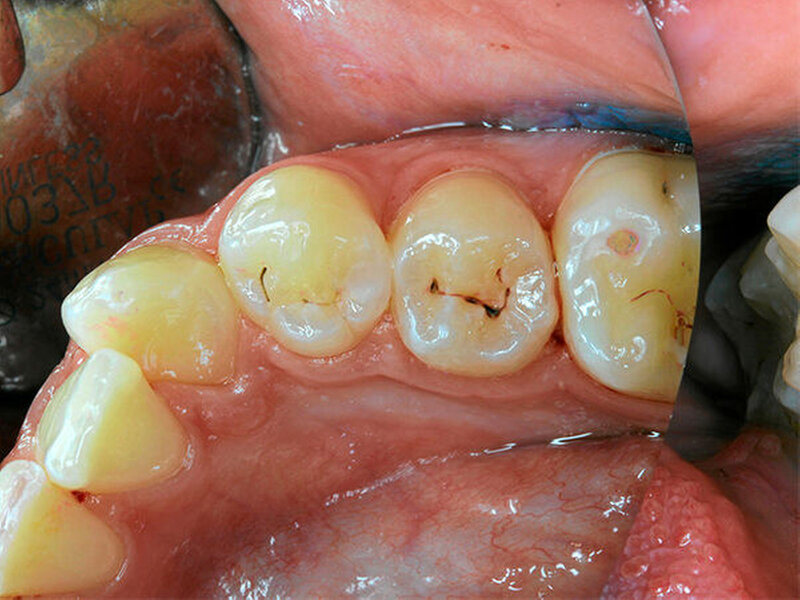

Bulk-Fill-Komposite gelten heute als etabliert, eignen sich aber nicht für alle Kavitäten. Was ist das Problem?

Bulk-Fill-Komposite sind für mich die erste Wahl für Füllungen im Prämolaren- und Molarenbereich: Die reduzierte Zahl von Inkrementen, die Möglichkeit, mit sogenannten Base-Kompositen zu arbeiten, die bei den Prämolaren dann ggf. noch mit einer hochästhetischen Deckschicht versehen werden können oder der Einsatz von thermoviskosen Produkten bei minimalinvasiver und defektorientierter Präparation führen zu hochwertigen Restaurationen, die sehr zeitsparend hergestellt werden können.